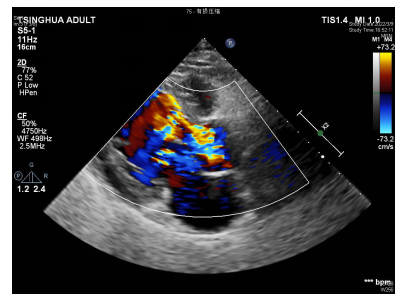

2)首先在全麻下行胸主动脉覆膜支架腔内隔绝术,锁骨下动脉支架置入术,烟囱技术左侧颈总动脉重建术。(如图4-A,B,C)